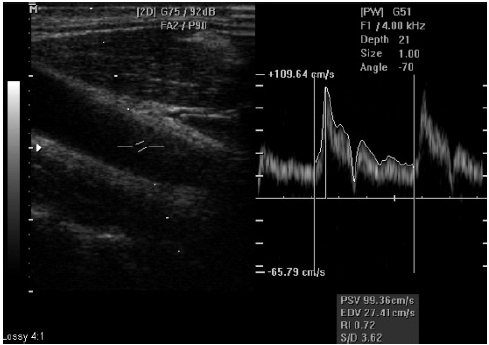

As modificações hemodinâmicas interpretadas pelo Doppler da artéria cerebral média fetal e artéria umbilical durante as insuficiências placentárias com repercussões hemodinâmicas fetais são

Avalie a imagem abaixo e marque a opção correta.